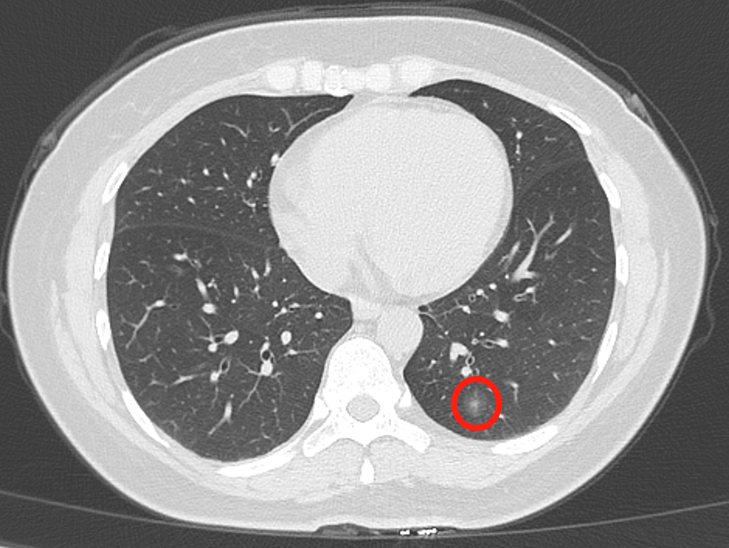

术 前

消融后,晕征范围完全覆盖结节位置